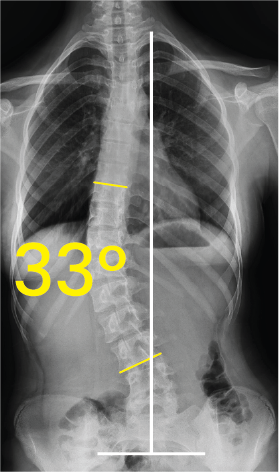

Bel omurgasında 33 derecelik eğrilik gösteren skolyozlu insan göğüs ve karın röntgeni.Göğüs bölgesinde 17 derece eğiklik gösteren omurga röntgeni görüntüsü.

Göğüs ve bel omurgasını gösteren röntgen görüntüsü, omurga eğrilik açısı 50 derece olarak işaretlenmiş.Torakal omurga röntgeninde 38 derece skolyoz açısı ve omurgada metal vida yerleşimi.